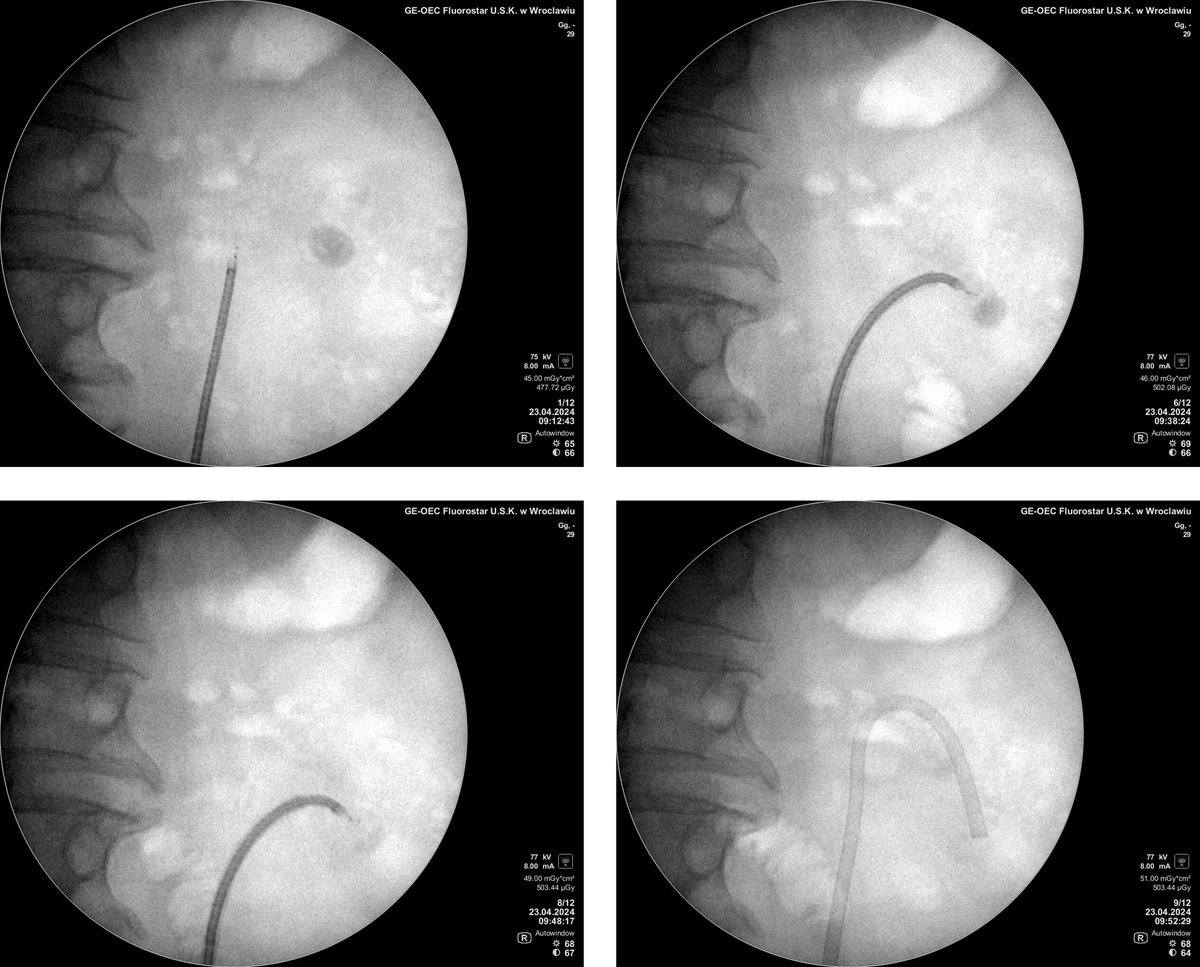

FANS are becoming a standard! Another step forward in providing top-notch care for our patients with urolithiasis! 1550 HU 20 x 17 mm stone removed in 42 min. 11/13 ClearPetra UAS 8.5 Fr Hawk ureteroscope @wojciechpiotrk1

@bartmalkiewicz

@ChorbinskaJ